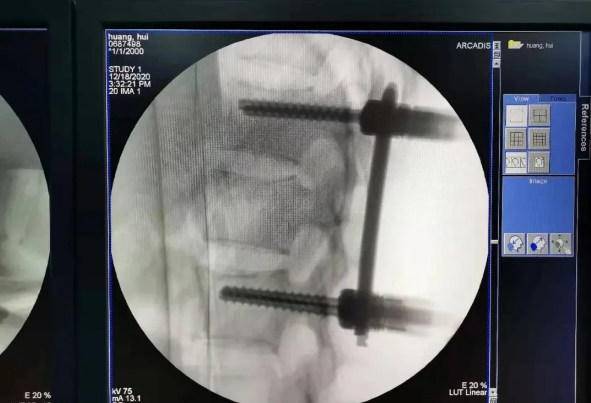

近日,天玑?骨科手术机械人落户南昌市第一医院,助力骨盆骨折闭合复位内牢固术顺利完成。作为江西省首先接纳5G引导下的骨科机械人手术,天玑?骨科手术机械人用它的“透视眼”,以三维影像扫描进行深层三维空间精准定位,为患者“量身定做”了最理想、最宁静的教科书般通道,完成了庞大骨盆骨折微创治疗一次性完美置钉及腰椎骨折微创经皮置钉的首秀,成为江西省骨科生长的标记性事件,同时也是江西省骨科步入新型数字智慧骨科时代的重要里程碑事件。

患者为22岁年轻女性,因车祸致骨盆骨折。骨盆骨折是一种庞大的创伤,古板手术方法需要比较大的切口,并且骨盆内有大宗庞大血管和神经,手术难度和危害极大,是许多骨科医生的禁区。

在古板骨科手术中,重复使用X线透视,有时须经常调解或更改手术牢固方法,经常需要多年的临床经验积累,也难免意外频发,究竟人眼判断和X线透视单平面视察的局限性是客观原因。

我国自主研发的天玑?骨科手术机械人,是针对骨骼硬组织的先进技术,已经获得国际认可,能够开展脊柱全节段 (颈椎、胸椎、腰椎、骶椎) 疾病、骨盆和四肢等骨折、骨肿瘤以及枢纽导航等手术。相比古板手术,机械人辅助手术具有手术创伤小、出血少、并发症少、康复快的优势。同时,由于不需通过重复透视来确定置钉位置,从而能减少术中辐射,大大降低患者辐射危害,且手术历程中,由机械人与主刀医师配合完成手术,大大增加了手术宁静性。

在南昌市第一医院廖琦教授领导下,由创伤骨科团队借助天玑?骨科手术机械人为患者“量身定做”最理想、最宁静的教科书般的通道,完美宁静微创完成手术,并且手术时间明显缩短,真正做到“指哪儿打哪儿”!更让患者定心的是,天玑?骨科手术机械人的“稳定手”机械臂进行精准定位,不必重复探寻。

由于天玑?骨科手术机械人的精准及高效,可以使手术时间明显缩短,因此在骨盆骨折手术后,在廖琦教授指导下,脊柱外科团队利用天玑?骨科手术机械人同样为20岁女性腰椎骨折患者“量身定做”最理想、最宁静的教科书般的通道,完美宁静微创完成手术,手术不但时间缩短,并且出血和透视减少。